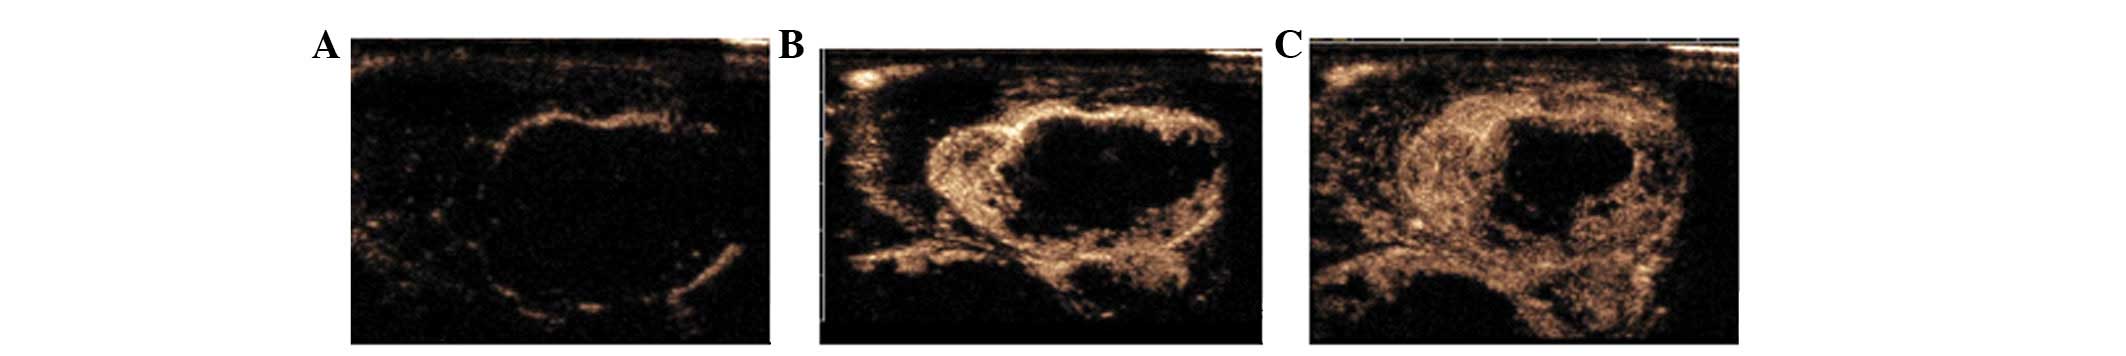

Contrast-enhanced ultrasonography of the rabbit VX2 tumor model: Analysis of vascular pathology

The accuracy of diagnosing tumors may be improved significantly by detecting the microvascular distribution. Indeed, contrast-enhanced ultrasonography (CEUS) has shown a distinct advantage in detecting microvasculature. This study aimed to determine the angiogenic characteristics of VX2 tumors in rabbits using CEUS. A total of 17 rabbits were injected with 0.5 ml VX2 cell suspension into the muscles of both hind legs to prepare the VX2 tumor models. At 14, 21, 28 and 35 days after tumor inoculation, CEUS was performed on the rabbits with 0.3 ml SonoVue following a local anesthesia. The pathological findings of the tumors were compared. A total of 12 rabbits survived after being inoculated with the tumor cells and developed a total of 38 tumors. The size of the tumors ranged from 1.12 to 10.85 cm. Using CEUS, all tumors demonstrated rim enhancement with some unenhanced regions. Enhancement began from the peripheral region and quickly showed internal reticular vessels. Regardless of the tumor size or the presence of necrosis, no complete enhancement of the tumors was observed. On microscopic examination, VX2 tumor cells were detected in striated muscles, immature blood capillaries and fibrosis tissues scattered in tumor nests. Immunohistochemical examination revealed that CD34+ cells appeared mainly in the muscles adjacent to vessels. In conclusion, CEUS may be an efficient method to evaluate angiogenesis and blood perfusion in VX2 tumors.